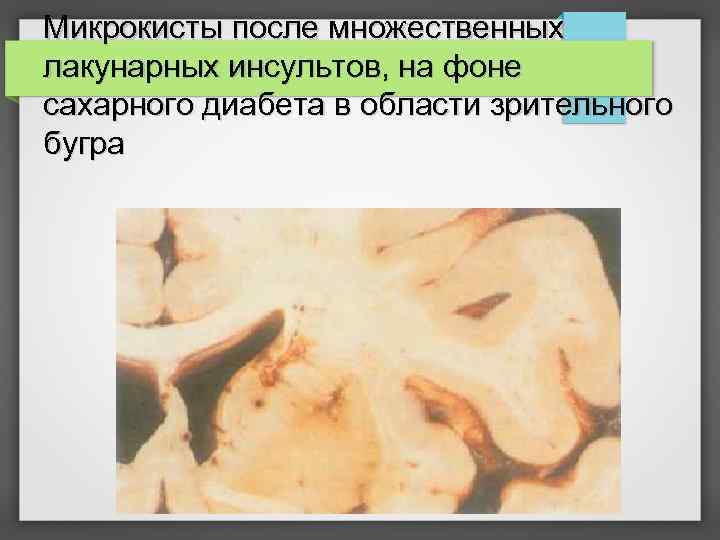

Микрокисты после множественных лакунарных инсультов, на фоне сахарного диабета в области зрительного бугра